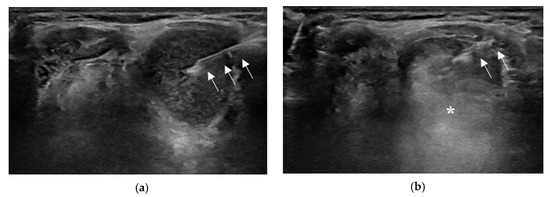

:1. Introduction

2.2. Aspiration of Internal Contents and Ethanol Injection

2.3.5. EA for TGDC with Viscous Internal Contents